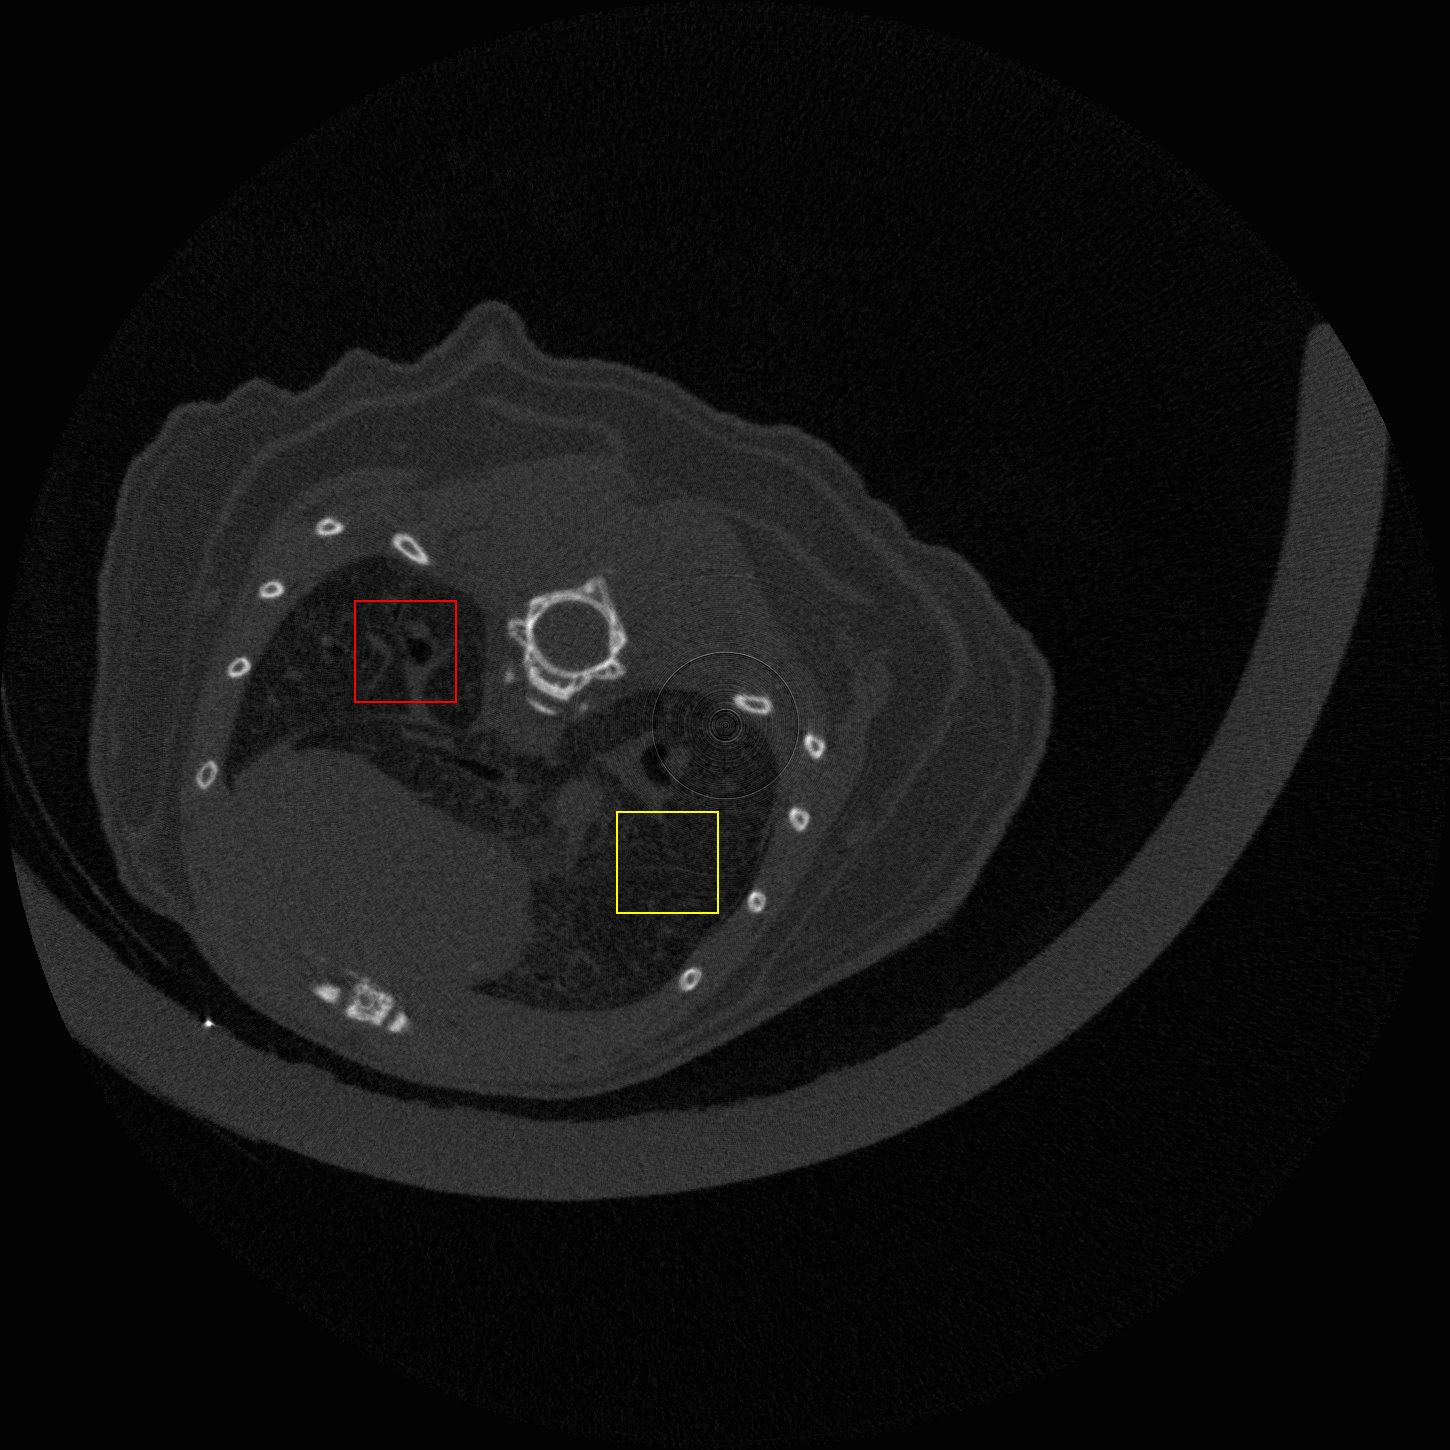

Figure 4: Visual comparsion of SRCT Case 111 from the Tibia dataset. The restored bony structures are shown in the red and yellow boxes in Fig. 5. The display window is [-900, 2000] HU.

Figure 5: Zoomed regions of interest (ROIs) marked by the red rectangle in Fig. 4. The restored image with GAN-CIRCLE reveals subtle structures better than the other variations of the proposed neural network, especially in the marked regions. The display window is [-900, 2000] HU.

III-D Experimental Results with the Tibia Dataset

We evaluated the proposed algorithms against the state-of-the-art algorithms on the tibia dataset. We present typical results in Fig. 4. It is observed that BM3D can effectively remove the noise, but it over-smoothens the noisy LR images. Then, the interpolation-based methods (NN+, Bilinear+, Bicubic+, Lanczos+) yield noticeable artifacts caused by partial aliasing. On the other hand, the DL-based methods suppress such artifacts effectively. It can be seen that our proposed GAN-CIRCLE recovers more fine subtle details and captures more anatomical information in Fig. 5. It is worth mentioning that Fig. 4 shows that there are severe distortions of the original images but SRGAN generates compelling results in Figs. 6-8, which indicate VGG network is a task-specific network which can generate images with excellent image quality. We argue that the possible reason is that the VGG network [68] is a pre-trained CNN-based network based on natural images with structural characteristic correlated with the content of medical images [80]. Fig. 5 presents that the proposed GAN-CIRCLEs can predict images with shaper boundaries and richer textures than GAN-CIRCLE, and GAN-CIRCLEu which learns additional anatomical information from the unpaired samples. The quantitative results are in Table II. The results demonstrate that the G-Forward achieves the highest scores using the evaluation metrics, PSNR and SSIM, which outperforms all other methods. However, it has been pointed out in [81, 82] that high PSNR and SSIM values cannot guarantee a visually favorable result. Non-GAN based methods (FSRCNN, ESPCN, LapSRN) may fail to recover some fine structure for diagnostic evaluation, such as shown by zoomed boxes in Fig. 5. Quantitatively, GAN-CIRCLE achieves the second best values in terms of SSIM and IFC. It has been pointed out in [83] that IFC value is correlated well with the human perception of SR images. Our GAN-CIRCLEs obtained comparable results qualitatively and quantitatively. Table II shows that the proposed semi-supervised method performs similarly compared to the fully supervised methods on the tibia dataset. In general, our proposed GAN-CIRCLE can generate more pleasant results with sharper image contents.